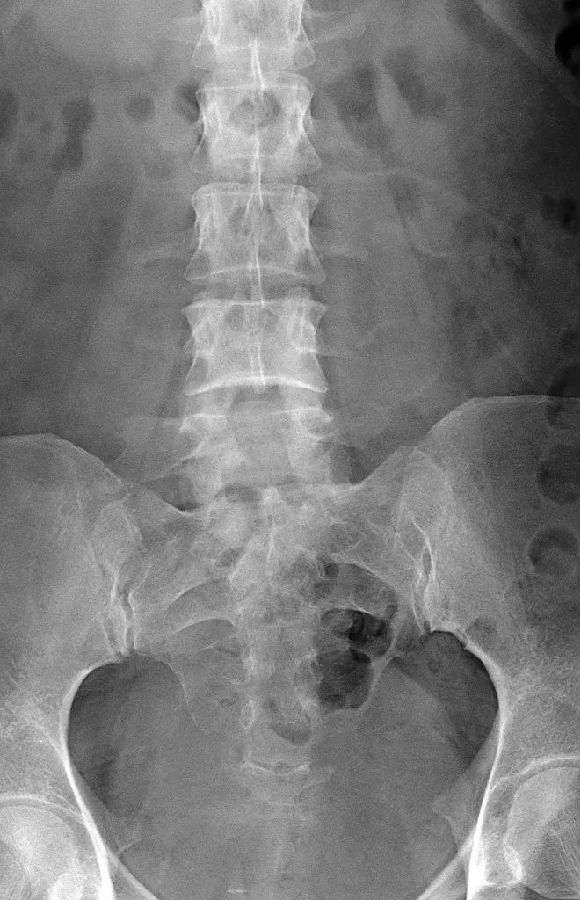

腰椎骶化及骶椎腰化均是椎骨发育的异常,腰椎骶化是指第五腰椎外型类似骶椎形态,并构成骶骨块的一部分,一侧或两侧横突肥大呈翼状,与骶骨发生融合或形成假关节。骶椎腰化是指第一骶椎演变成腰椎样形态,即第一骶骨从筋骨块中游离出来形成第6个腰椎。

这是一个最关键和准确的鉴定方法,国内著名骨放射学家杨世埙教授指导过,只要大家留意关注腰椎横突"三长/四翘/五宽",L3横突是最长的,L4横突是上翘的,L5横突最宽,特别用在胸椎腰化合并L5骶化的时候比较实用。

目前,腰骶移行椎以Castellvi的分类方法最为常用。其主要根据横突形态及其与骶骨、髂骨是否融合或形成假关节而分为4型,Ⅰ、Ⅱ、Ⅲ型又根据单、双侧分为A、B两个亚型。

I型:主要为腰5横突发育不良,横突宽度大于19mm,并将其分为两个亚型Ia(单侧横突发育不良)或Ib(双侧横突发育不良)

L5右侧横突肥大,为Ⅰa型

L5双侧横突肥大,为Ⅰb型

II型:表现为不完全的腰椎骶化,具有增宽的横突,并且和骶骨形成假关节,并将其分为两个亚型IIa(单侧关节形成)或IIb(双侧关节形成)

L5左侧横突肥大,假关节形成,为Ⅱa型

L5双侧横突肥大,假关节形成,为Ⅱb型